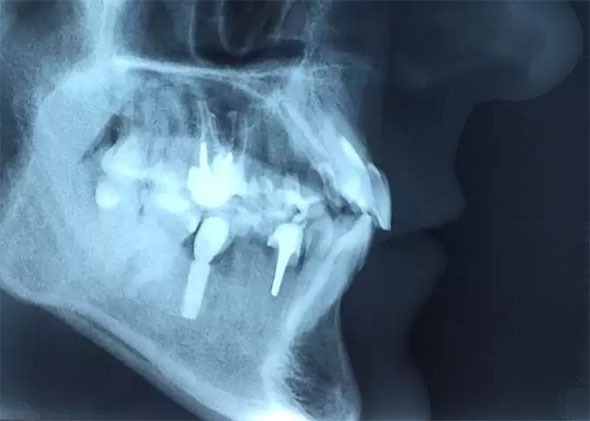

Panoramic X-ray (so-called panorama):

Cephalometric X-ray (so-called lateral):